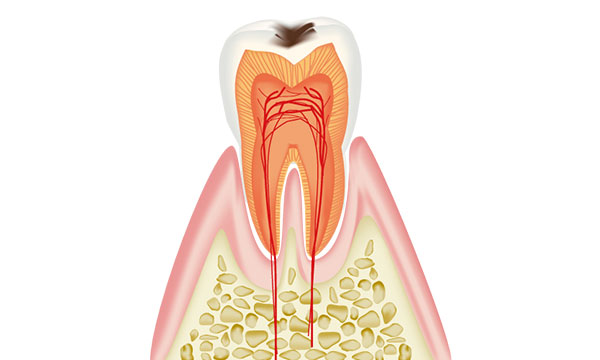

虫歯は進行の程度で5段階に分けられます。

さらに虫歯が進行してエナメル質の内側の象牙質に達すると痛みがでます。噛んだ時や甘いものを食べたとき、冷たいものを飲んだときなどに痛みを感じます。この象牙質は柔らかい組織で虫歯に弱いため、虫歯の進行が早くなります。

歯に痛みを感じたら、一度歯科での受診をおすすめします。